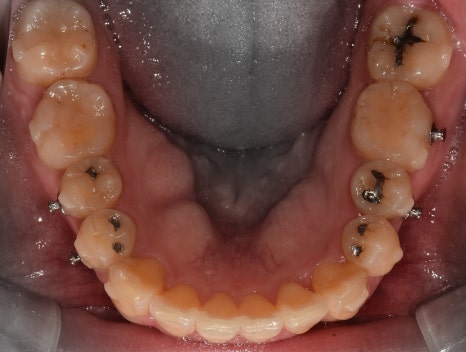

그러면서, 대략 2년이라는 시간이 흘러서

가지런한 치열이 탄생이 되었습니다.

앞서, 1치대 1치 관계에 있던 교합관계들이

1치대 2치의 관계로 바뀐것을 볼 수 있으면서

길쭉하게 느껴졌던, U shape 형태의 악궁이

딱 보기 좋은, U shape 로 바뀌었죠.